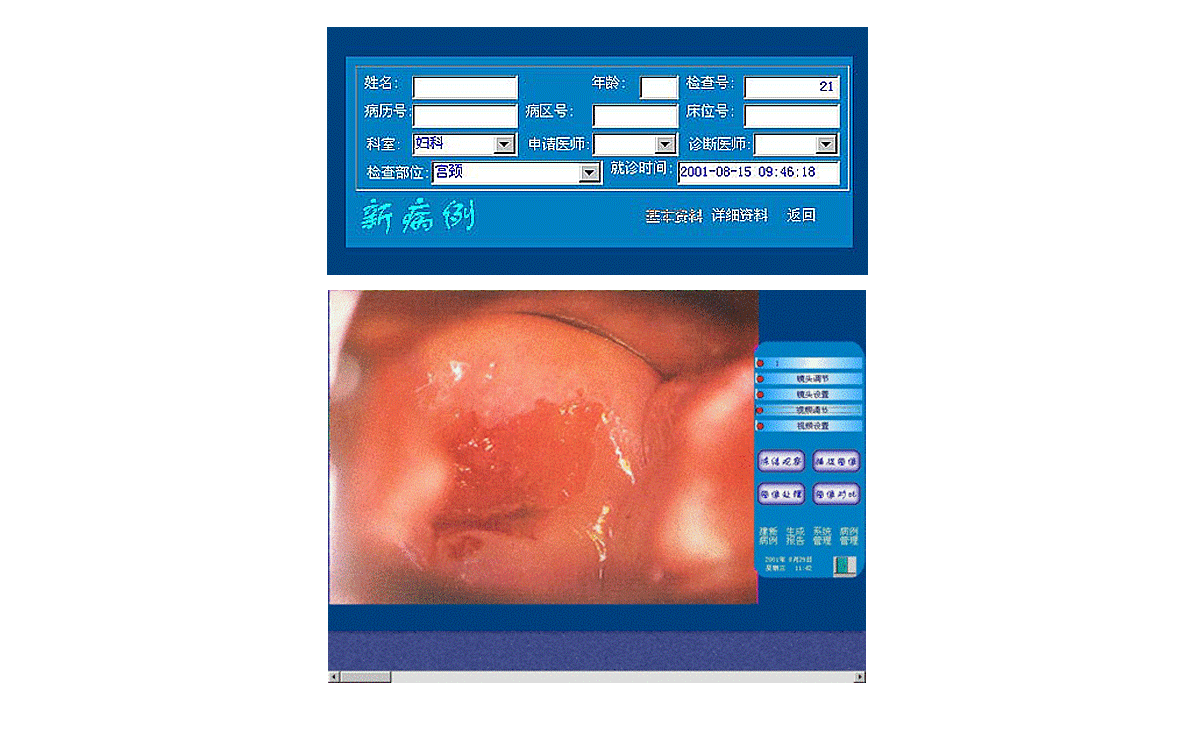

3、打開顯視器電源開關(guān),開啟主機電源總開關(guān),開啟陰道鏡系統(tǒng),待系統(tǒng)進入正常窗口界面后,先創(chuàng)建新病例,通過觀察、采集、生成報告后,即可完成整個陰道鏡檢查與診斷操作。

2、用鼠標(biāo)點擊主界面窗口中<建新病例>按鈕后輸入病人的一些資料,再點擊該窗口上的<返回>按鈕,系統(tǒng)進入圖像采集窗口界面,這時圖像采集窗口將顯示陰道鏡所觀察到的動態(tài)影像。